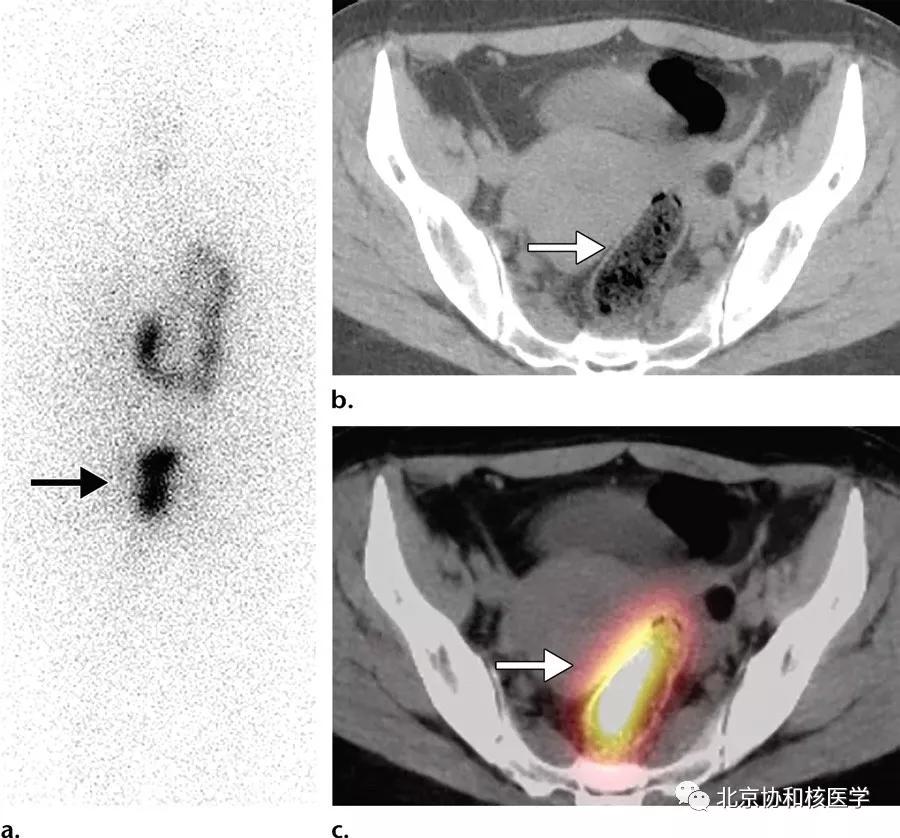

36岁女性,乳头状甲状腺癌甲状腺全切除术后,碘131治疗后7天显像见子宫内膜区摄取,考虑为碘在经血中滞留所致: